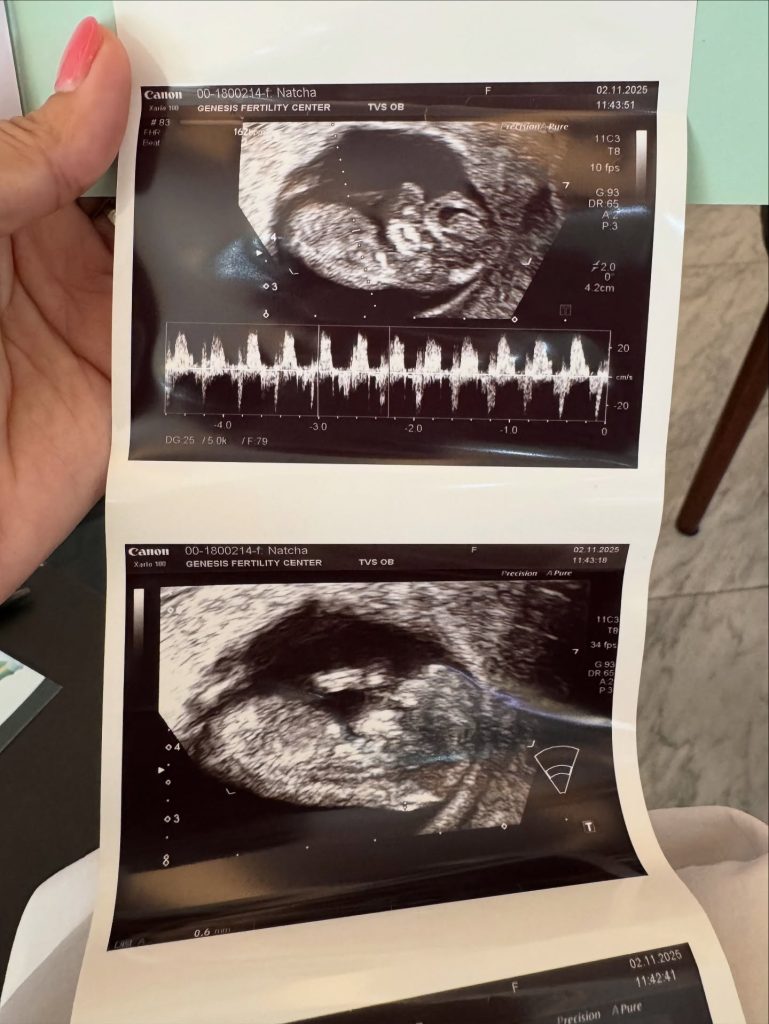

เรียกได้ว่าเป็นคุณแม่หัวใจนักวิทยาศาสตร์ที่ทั้งเก่งและแกร่ง สำหรับ “ครูก้อย–นัชชา ลอยชูศักดิ์” ภรรยาของนักร้องดัง “เจมส์ เรืองศักดิ์ ลอยชูศักดิ์” ที่สามารถฝ่าฟันอุปสรรคท้องยากหลายอย่างกว่าจะมีเบบี๋คนที่ 2 ในวัย 42 ปี โดยครูก้อยได้โพสต์อัปเดทการพักฟื้นหลังจากการเข้ารับการเย็บปากมดลูก ผ่านเฟซบุ๊ก “นัชชา ลอยชูศักดิ์” ขณะตั้งครรภ์ได้เพียง 3 เดือน เนื่องจากมีภาวะปากมดลูกสั้น ซึ่งการรักษาผ่านไปได้ด้วยดี ทั้งนี้ ครูก้อยเคยมีประสบการณ์เข้ารับการเย็บปากมดลูกมาแล้วเมื่อตอนตั้งครรภ์ลูกสาวคนแรก “น้องเมดา อันโดรเมดา” จึงทำให้ครูก้อยไม่ลังเลในการเข้ารับการเย็บปากมดลูกในครั้งนี้ โดยครูก้อยไม่รอให้มีอาการก่อนค่อยรักษา แต่ตัดสินใจเย็บปากมดลูกเลย เพื่อป้องกันทุกความเสี่ยงอย่างรอบคอบที่สุด

นอกจากนี้ ครูก้อยยังได้เปิดเผยถึงอุปสรรคที่ได้ฝ่าฟันมาจนกว่าจะตั้งครรภ์ลูกคนที่ 2 ว่า ตอนนี้ตั้งครรภ์ได้ 12 สัปดาห์แล้ว โครโมโซมปกติทุกคู่ น้องเป็นผู้หญิง ชื่อ ด.ญ.มีเมตตา ลอยชูศักดิ์ (น้องเมตตา) เป็นการใส่ตัวอ่อนครั้งที่ 2 ในวัย 42 ปี โดยครั้งแรกใส่ตัวอ่อนไปเมื่อ 6 เดือนก่อน แต่น้องอยู่กับครูก้อยได้ไม่นาน ก็หลุดไป ครูก้อยไม่มีเวลาเสียใจแม้แต่วันเดียว เพราะภารกิจที่ยิ่งใหญ่มีมากกว่านั้น ครูก้อยมีแม่ๆ ผู้มีบุตรยากอีกหลายหมื่นคนที่ยังร่วมเดินทางบนเส้นทางเดียวกันที่ต้องดูแล เดินหน้าดูแลสุขภาพและบำรุงร่างกายต่อก่อนย้ายตัวอ่อนครั้งที่ 2 ในวัย 42 จนประสบความสำเร็จ และเชื่อมั่นว่า “น้องเมตตา” จะเติบโตเป็นนักสู้ตัวน้อยที่เข้มแข็งไม่แพ้คุณแม่อย่างแน่นอน